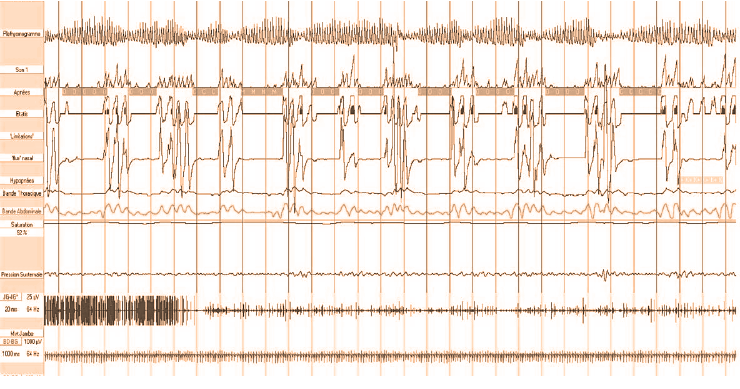

3. Polisonnografia notturna con sistema portatile L’evoluzione tecnologica ha consentito di produrre sistemi di registrazione più articolati dei precedenti, ma sempre portatili; con questi apparecchi è possibile la registrazione dei seguenti parametri: elettroencefalogramma, elettrooculogramma, elettromiografia sottomentoniero, rumore respiratorio, flusso aereo oro-nasale, movimenti respiratori toracici ed addominali, elettrocardiogramma, ossimetria, posizione corporea, il movimento degli arti. E’ consentità così la stadiazione del Sonno, il riconoscimento degli elementi microstrutturali e la identificazione diretta degli eventi respiratori, ma non è prevista la sorveglianza del paziente e della qualità del tracciato per tutta la notte.